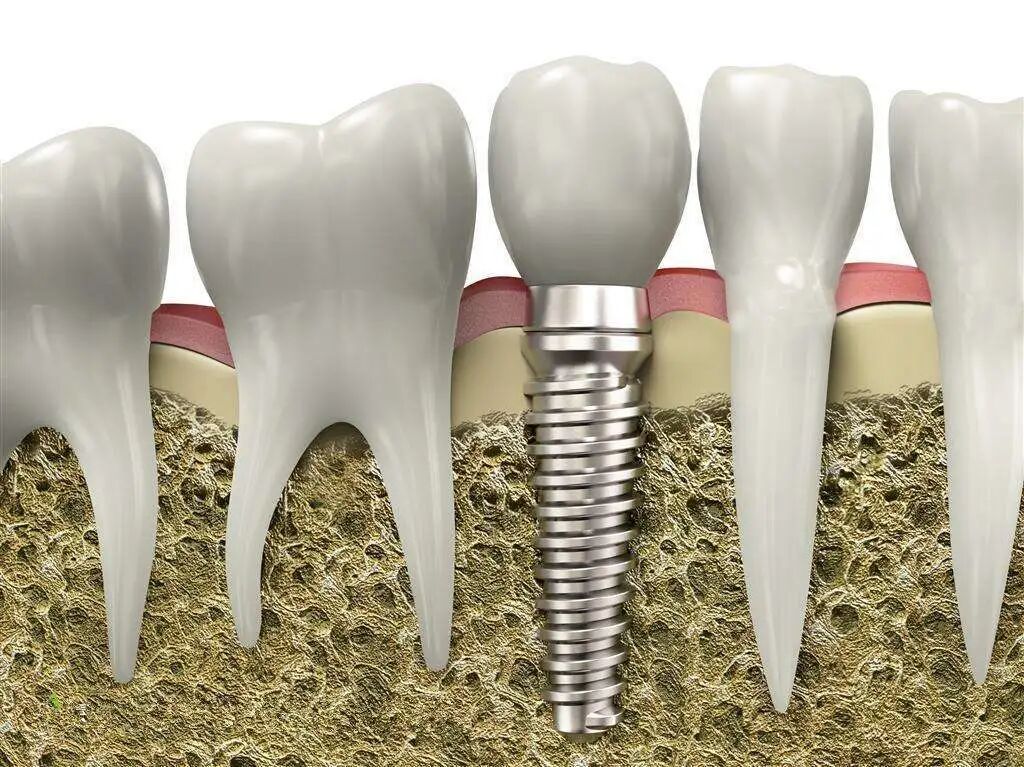

所以,千万不要谈“手术”色变,毕竟再贵的种植牙,也不如健康的天然牙好使,如果有机会,就需要患者和医生共同努力,把牙留住!

电刀怎么洗我以为只要洗个牙,医生你怎么还拿起了手术刀?_https://www.jmylbn.com_新闻资讯_第9张